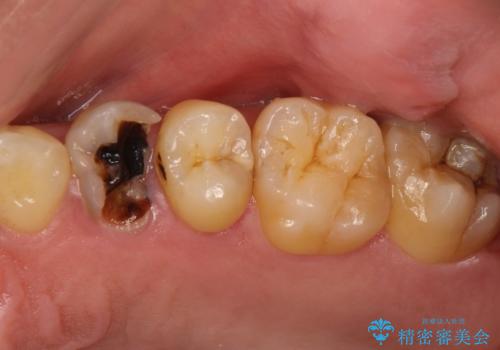

[フルジルコニアクラウン] 老朽化した銀歯を白く